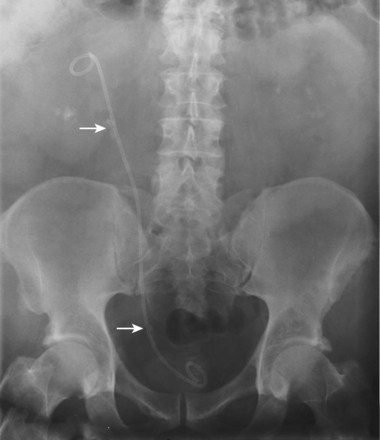

The plain abdominal radiograph is a conventional radiography study, which, in urology, is intended to display the kidneys, ureters and bladder. The plain abdominal radiograph may be employed (1) as a primary study or (2) as a scout film in anticipation of contrast media. Plain films are widely used in the management of renal calculus disease. Plain radiography is also useful in evaluation of the trauma patient because it can be performed as a portable study in the trauma unit. Secondary findings on plain radiography such as rib fractures, fractures of the transverse processes of the vertebral bodies, and pelvic fractures may indicate serious associated urologic injuries.

An abdominal plain radiograph is obtained with the patient in the supine position, using an anterior to posterior exposure. The study typically includes that portion of the anatomy from the level of the diaphragm to the inferior pubic symphysis. It may occasionally be necessary to make two exposures to cover the desired anatomic field. Depending on the indication for the study, oblique films are obtained to clarify the position of structures in relation to the urinary tract. If small bowel obstruction or free peritoneal air is suspected, upright films will be obtained.

Although plain film radiography is often used in the evaluation of renal colic, it is unreliable in the demonstration of calculus disease for various reasons: (1) overlying stool and bowel gas may obscure small calculi; (2) stones may be obscured by other structures such as bones or ribs (Fig. 4–4); (3) calcifications in pelvic veins or vascular structures may be confused with ureteral calculi; and (4) stones that are poorly calcified or composed of uric acid may be radiolucent. Nevertheless, plain film radiography is valuable in assessing the suitability of a patient for extracorporeal shock wave lithotripsy because the ability to identify the stone on fluoroscopy is critical to targeting. Furthermore, a KUB film is cost-effective for monitoring residual stone burden after treatment (Fig. 4–5). For complex pathology of the urinary tract, plain abdominal radiography has been supplanted by axial imaging. Plain radiography has a limited role in evaluating soft tissue abnormalities of the urinary tract.